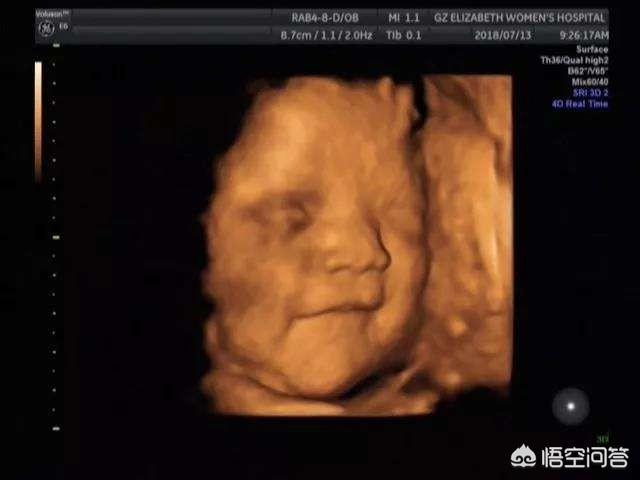

可以明确的一点是胎儿在子宫内是会开心的。这最明显的证明就是有时在做四维彩超时可以拍到宝宝微笑的表情,这足以说明胎儿在子宫内是会开心的。

其实除了微笑,胎儿还有别的表情,比如生气、哭泣等等。